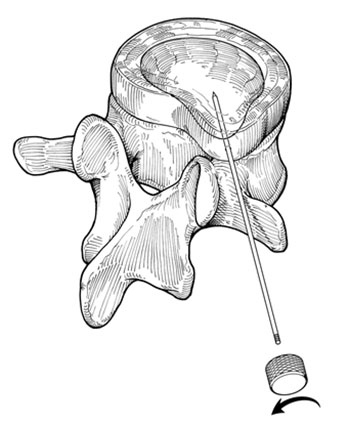

Após a introdução do fio guia procede-se com o dilatador, seguido da cânula, para finalmente poder introduzir o microressector, aparelho com o qual é realizada a ressecção do conteúdo do disco (Fig 5 a-e).

Fig. 5a